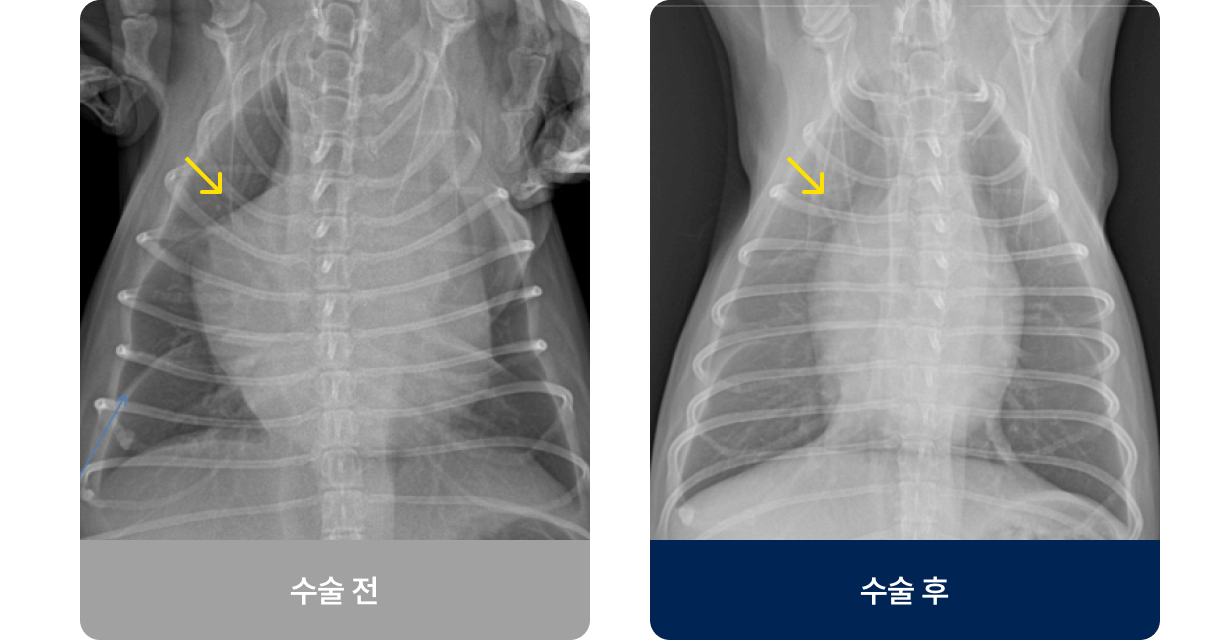

횡격막(가슴과 배를 구분하는 근육)에 구멍이 생겨, 간·위·장기 같은 복부 장기가 흉강 안으로 들어간 상태로, 이는 폐를 압박하고 폐가 완전히 팽창하지 못하게 하여 호흡 곤란을 유발합니다. 주로 교통사고나 낙상 등의 외부 충격으로 발생하며 호흡곤란, 구토, 식욕 저하 증상을 보입니다.